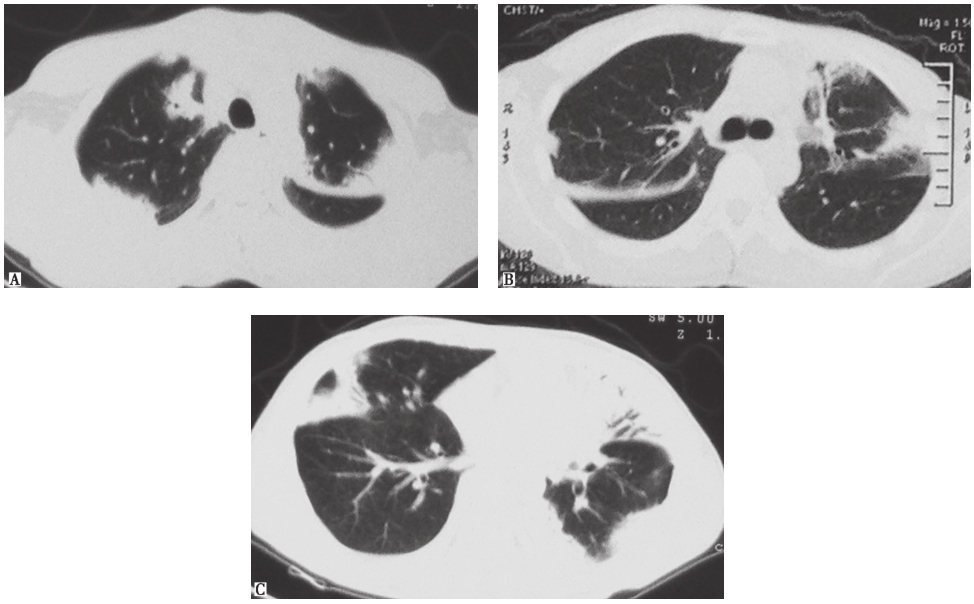

患者入院进行抗感染治疗(阿莫西林克拉维酸、亚胺培南西司他丁)10天后,复查胸部CT(2013年1月14日),提示双肺原有实变病灶较前(2013年1月4日)略有进展(图2)。

图2入院治疗10天后复查胸部CT表现